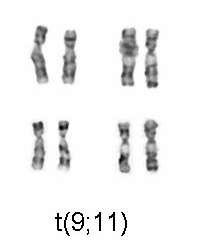

| M5 | acute monoblastic leukemia (M5a) or acute monocytic leukemia (M5b) | del (11q), t(9;11), t(11;19) | 10%[28] |

Specific cytogenetic abnormalities can be found in many people with AML; the types of chromosomal abnormalities often have prognostic significance.[33] The chromosomal translocations encode abnormal fusion proteins, usually transcription factors whose altered properties may cause the "differentiation arrest".[34] For example, in acute promyelocytic leukemia, the t(15;17) translocation produces a PML-RARα fusion protein which binds to the retinoic acid receptor element in the promoters of several myeloid-specific genes and inhibits myeloid differentiation.[35]

The single most important prognostic factor in AML is cytogenetics, or the chromosomal structure of the leukemic cell. Certain cytogenetic abnormalities are associated with very good outcomes (for example, the (15;17) translocation in acute promyelocytic leukemia). About half of people with AML have "normal" cytogenetics; they fall into an intermediate risk group. A number of other cytogenetic abnormalities are known to associate with a poor prognosis and a high risk of relapse after treatment.[60][61][62]

| Good | t(8;21), t(15;17), inv(16) | 70% | 33% |